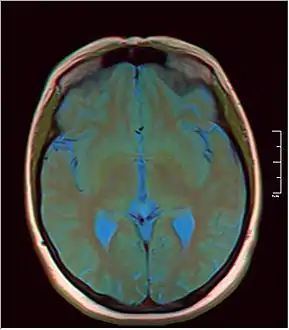

Additional images

MRI axial in false color